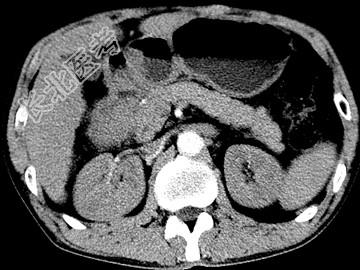

- 单项选择题女,63岁, 右上腹疼痛,呈不规律性钝痛, 伴恶心,时有呕吐, 呕吐物为胃内容物混有胆汁,CT检查如图, 最可能的诊断是 ( )

A、十二指肠克罗恩病

B、十二指肠结核

C、十二指肠癌

D、十二指肠淋巴瘤

E、十二指肠平滑肌瘤